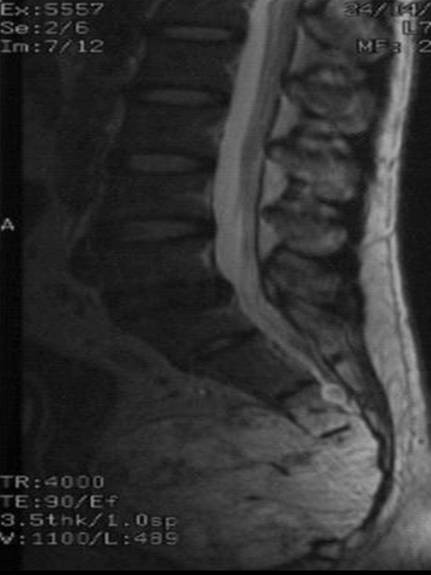

Hypersignal on T1WI

T1W FASAT CE